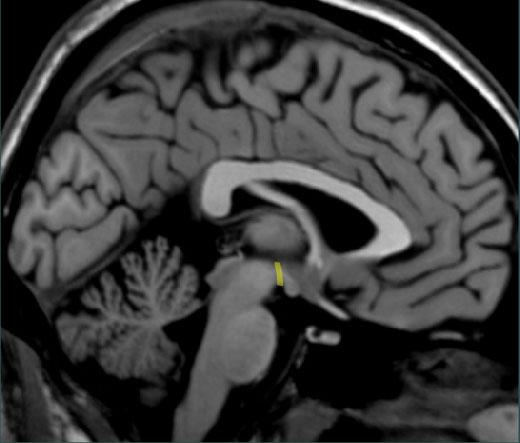

Correct! The boundary between the midbrain and the hypothalamus is highlighted.